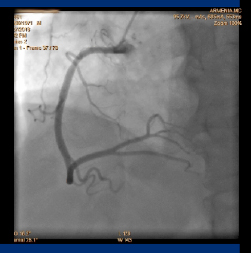

Նույն օրը` ապրիլի 19-ին իրականացվել է սելեկտիվ ռեկորոնարոգրաֆիա: Արդյունքում հայտնաբերվել է, որ կորոնար անոթավորումն աջ դոմինանտ տիպի է, ձախ առաջային վայրէջ կորոնար զարկերակը (LAD) աթերոսկլերոտիկ ախտահարված է, մոտակա-միջին հատվածում վաղ իմպլանտացված ոչ դեղապատ ստենտը տոտալ խցանված է ՝100% թրոմբոտիկ զանգվածի առկայությամբ: Գոտևորող կորոնար զարկերակը (CX)-աթերոսկլերոտիկ ախտահարված է՝ առանց տեսանելի նեղացումների, աջ կորոնար զարկերակը (RCA) աթերոսկլերոտիկ ախտահարված է՝ առանց տեսանելի նեղացումների:

Շտապ կատարվել է Ձախ առաջային վայրէջ կորոնար զարկերակի (LAD) ռեվասկուլյարիզացիա եւ բազմակի բալոն դիլատացիա:

Ինտուբացվել է Ձախ կորոնար զարկերակի հիմնական ցողունը (LM):

Լարն անցել է (LAD) հեռակա հատվածները:

Կատարվել է (LAD) մոտակա եւ միջին հատվածների in stent բազմակի բալոն դիլատացիա Medtronic Solarice 3.5 mm x 20 mm բալոնով:

Արդյունքում վերականգնվել է արյան անտեգրատ հոսքը (TIMI III):

Վիրահատությունն իրականացրել է ինտերվենցիոն սրտաբան Պողոս Հրայրի Սարգիսյանը: